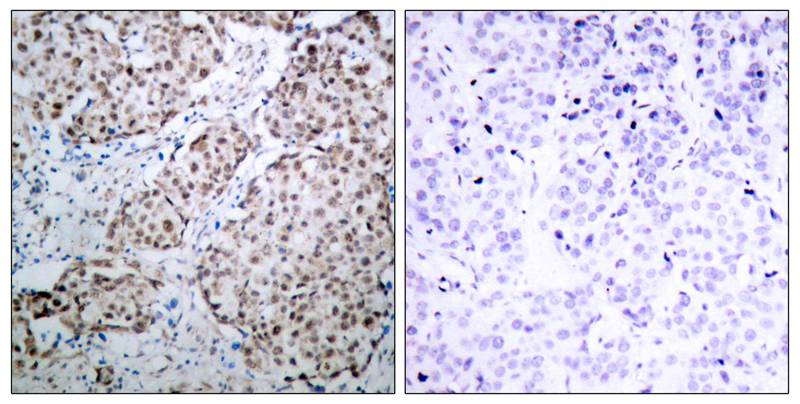

分类: 科研抗体货号: P40047别名: SLEB11应用: WB,IHC反应种属: Human,Mouse,Rat